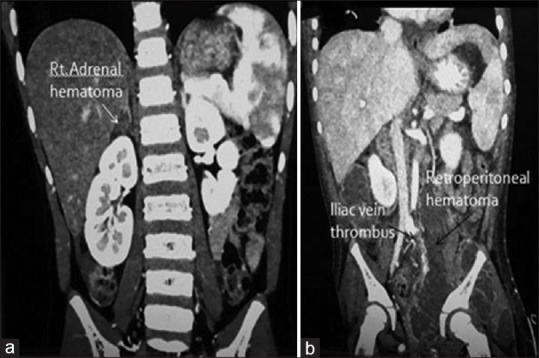

Results: A total of 68 patients were included in the study. Fall from height was the most common mode of injury (62%) followed by road traffic accidents (35%) and the other causes included in the miscellaneous group (hit by animal and fall of heavy object on the abdomen; 3%). Most commonly injured organ was liver (n = 28, 41%) followed by spleen (n = 18, 26%) and kidney (n = 15, 22%). Other injuries were bowel perforations (jejunal [n = 4], ileal [n = 1] and large bowel [n = 1]; 9%), pancreaticoduodenal (n = 5, 7%), urinary bladder (n = 3, 4%), abdominal vascular injury (iliac vein-1, inferior vena cava-1;3%), adrenal haematoma (n = 2,3%) and common bile duct (CBD) injury (n = 1, 1%). More than one organ injury was seen in 13 cases (19%). Non-operative management was successful in 84% (n = 27) and laparotomy was done in 16% (n = 11). Most of the patients sustained Grade IV injury (n = 36, 53%) and majority of the patients (n = 60, 88%) had good outcome without any long-term complications.